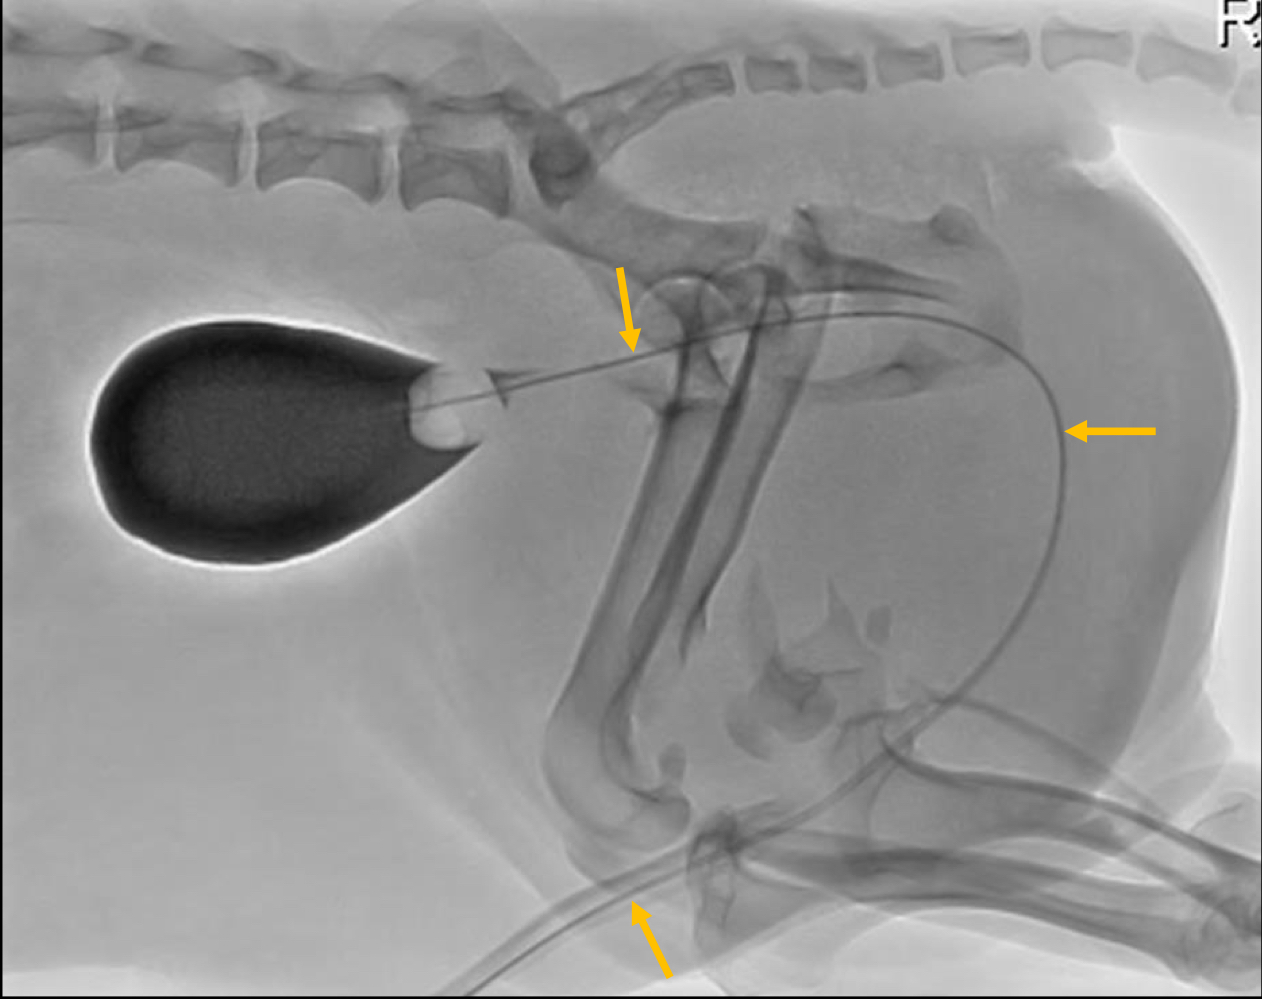

What is being pointed to in this cystourethrograph?

positive iodine contrast